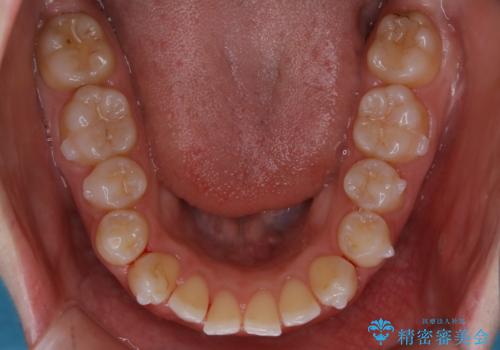

【非抜歯】上下の前歯が噛み合わないオープンバイトの治療

- 噛み合わせの不調を主訴にご来院されました。

骨格的な問題もあり、噛んだ時に奥歯しか当たらず前歯の被蓋があまりない状態でした。

奥歯を沈めて噛み込みを深くしていくことで被害の改善が起こるとともに、下顎自体が前上方に回転移動することで顔貌的にも変化を出すことができます。

臼歯の位置が高く噛んだ時に奥歯しか当たらなかったり、舌癖などが原因で前歯が前に倒れてしまうことで上下の前歯の被蓋がなくなってしまっている状態をオープンバイトといいます。

前者の場合は臼歯を圧下し沈めてあげることで改善させます。後者の場合は前方に傾斜している歯を元の角度に戻してあげることで改善しますが、舌癖がある場合はその癖自体を無くす治療をしない限りまた同じ状態へと後戻りしてしまいます。